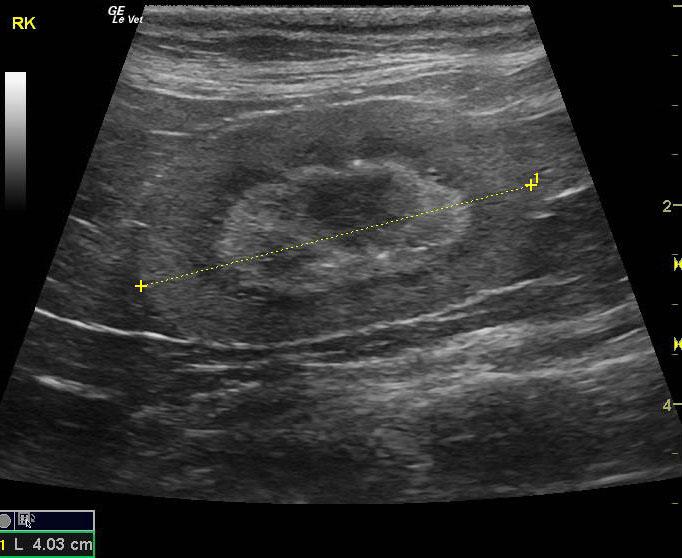

A 16-year-old spayed female cat was presented for evaluation of hematuria and inappropriate urination. On urinalysis, an inappropriate specific gravity (1.014) and hematuria were evident. The only abnormality on blood work was mild anemia.

A 16-year-old spayed female cat was presented for evaluation of hematuria and inappropriate urination. On urinalysis, an inappropriate specific gravity (1.014) and hematuria were evident. The only abnormality on blood work was mild anemia.